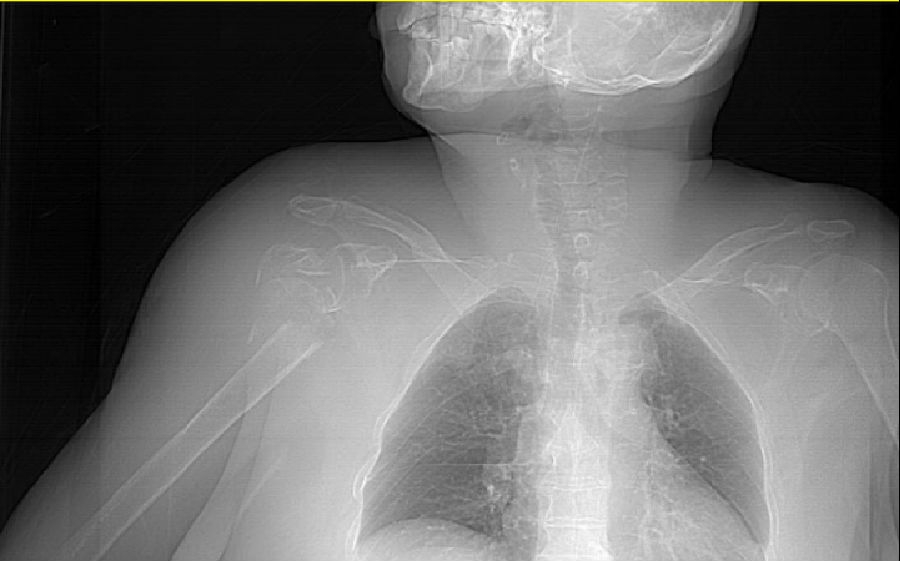

术前腕关节CT

2、左桡骨远端骨折